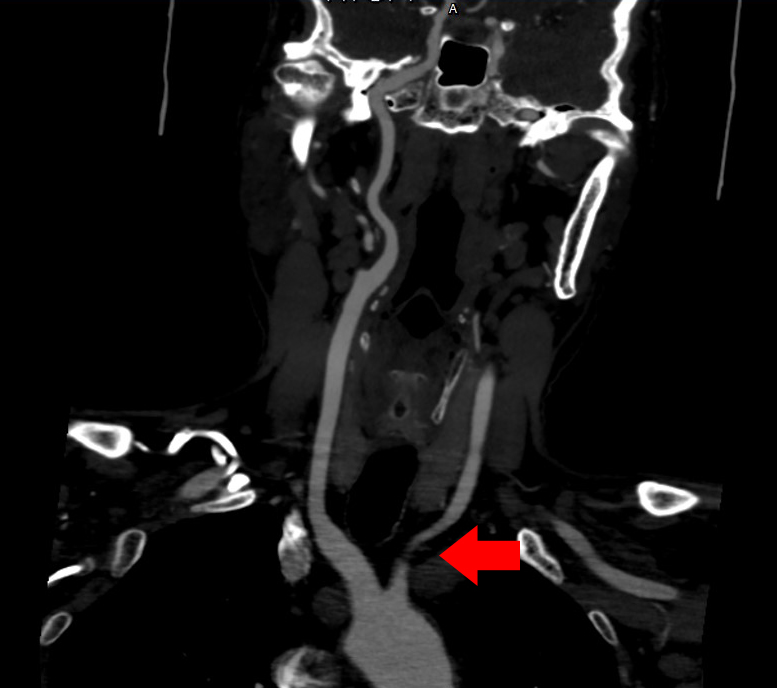

近期,东北国际医院神经外科接诊了一例左侧锁骨下动脉闭塞盗血综合征患者。该名患者近五年来走路不稳,最近一年自觉头晕伴左上肢麻木。神经外科医生检查后发现,患者左臂血压107/75mmHg、右臂血压140/84mmHg,左右手臂血压差别明显。辅以彩超检查及DSA血管造影,提示:左侧椎动脉血流频谱完全逆转,左侧锁骨下动脉近端闭塞,盗血形成,最终确诊为锁骨下盗血综合征伴锁骨下动脉闭塞。

DSA:锁骨下动脉局部狭窄

明确诊断后,神经外科为患者行左侧锁骨下动脉狭窄支架置入术。术后造影,闭塞解除,血管通畅。患者双侧上肢血压恢复一致,神清语明,四肢活动自如。

释放支架术后检查:狭窄处支架成型